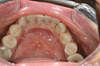

APRES